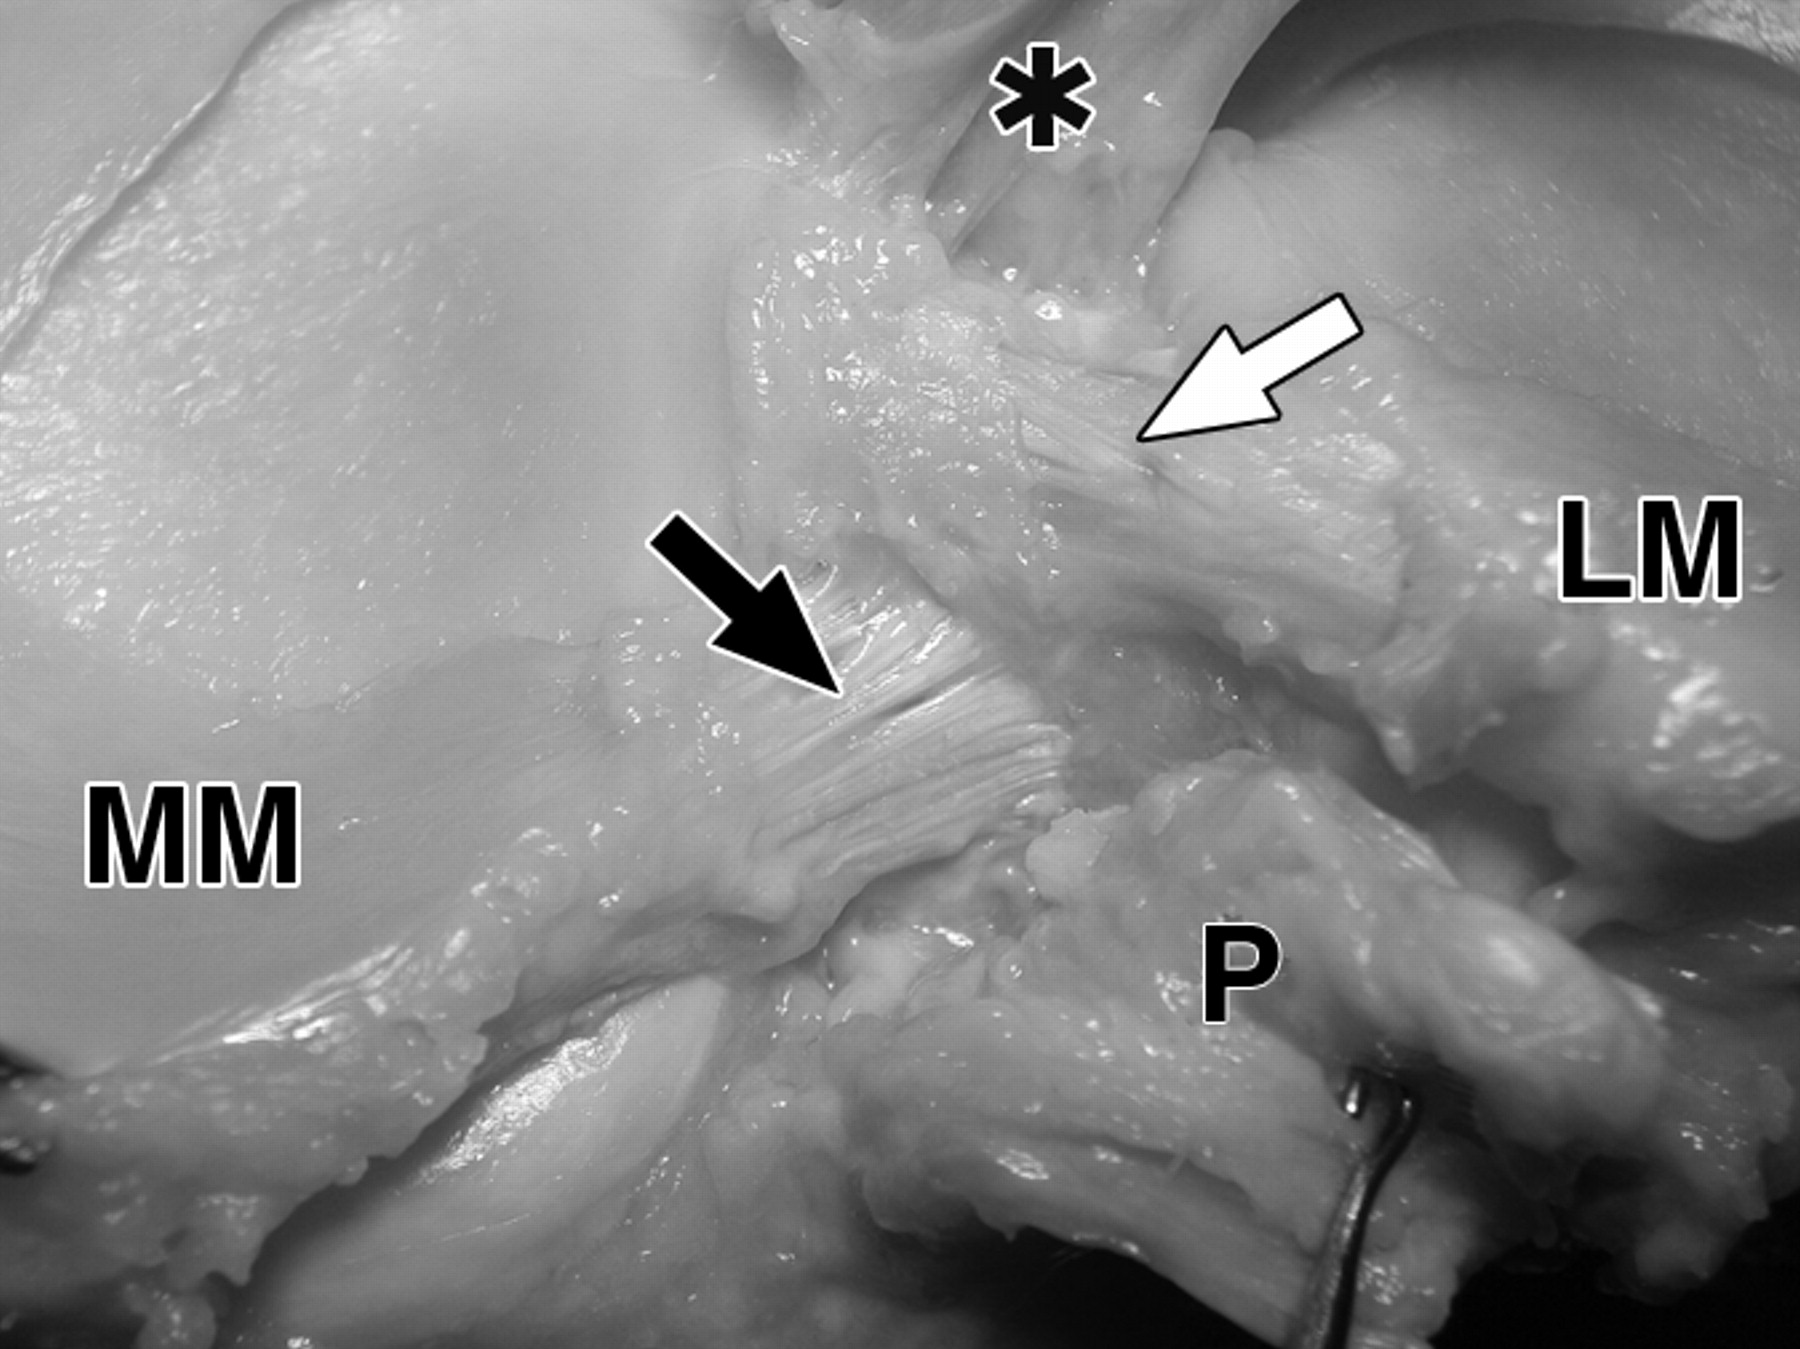

图4 B-59岁男性大体标本。

照片显示了前、后交叉韧带胫骨止点的解剖关系。

膝关节后视图显示外侧半月板后根(LM)(白色箭头)的止点比内侧半月板后根(MM)(黑色箭头)和后交叉韧带(P)的止点更靠前。前交叉韧带止点(星号)在结节间嵴的前面,但由于摄影变形,看起来更靠近外侧半月板后根。